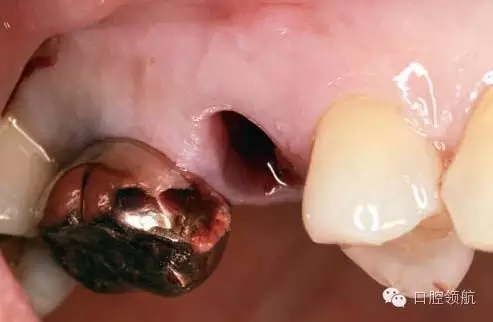

患者10年前,在外院于( 左上第六顆牙)區(qū)行上頜竇底提升術(shù)同期植入種植體,經(jīng)過10年上頜竇內(nèi)生成骨完全吸收消失了(圖1)?;颊叽舜蝸碓菏且驗猷徰? 左上第五顆牙) 不能保存,希望行種植修復(fù)治療。

術(shù)前口內(nèi)未見種植體周圍有炎癥等異常表現(xiàn)(圖2),翻開黏骨膜瓣后,10年前手術(shù)入路的痕跡在頰側(cè)骨面已經(jīng)觀察不到了(圖3)。

圖2 ( 左上第五顆牙)拔除后即刻的口內(nèi)像。